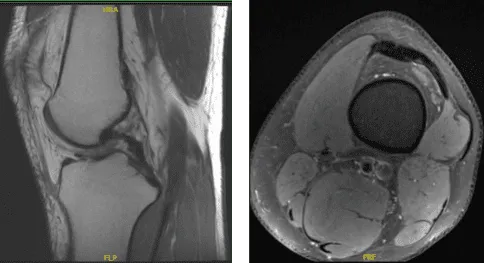

MRI Impression as follows: Oblique tear in the posterior horn of the medial meniscus extending to the inferior surface, peripheral third. Edema in the superolateral aspect of Hoffa’s fat pad suggestive of Hoffa’s fat pad impingement and elevated TT TG distance of 16 mm which can be seen in setting of patellofemoral maltracking and small popliteal cyst.

MRI of the back spine